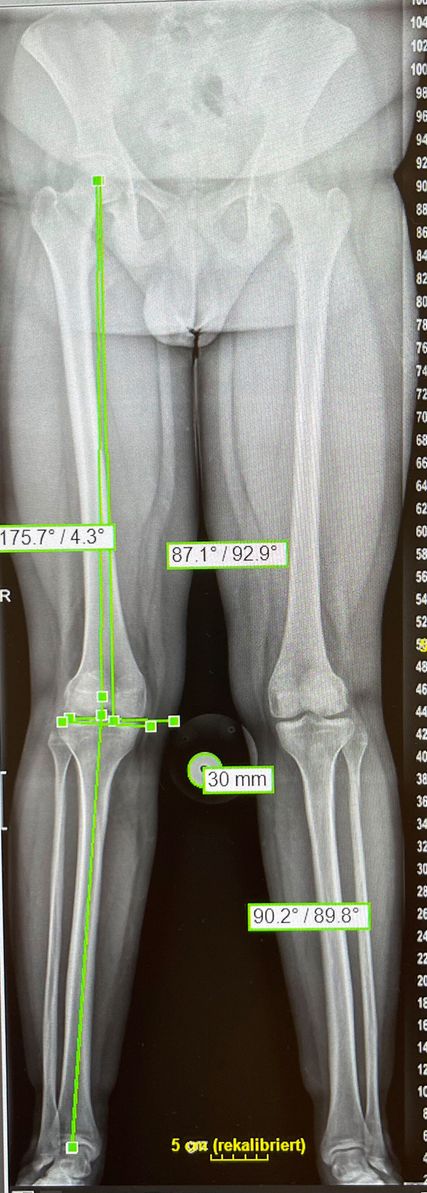

Abb. 3: Eine vermehrte Innenrotation von Femur/Tibia sowie eine valgische Beinachse können Faktoren für eine Patellainstabilität sein

Eine Instabilität bis circa 30° ohne weitere Auffälligkeiten in der radiologischen Untersuchung wird mittels alleiniger MPFL-Rekonstruktion stabil. Ab circa 0–60° Instabilität gibt es zumeist Probleme mit der knöchernen Führung. Dies kann aufgrund eines zu späten Eingleitens der Patella – einer Patella alta – und/oder des Fehlens einer knöchernen Führung (Trochleadysplasie) auftreten. Unserer Meinung nach bedarf es einer Korrektur der Patella alta ab einem Caton-Deschamp-Index >1,2 (Abb.1) und/oder einer LTI (laterale Trochleainklination) von <17° (Abb. 2). Ab 60° ist zusätzlich ein Problem im Bereich des Alignments wahrscheinlich. Bei einer vermehrten Innenrotation des Femurs und der Tibia bei ca. 35° und/oder valgischer Beinachse ab ca. 5° wird eine Korrektur in Erwägung gezogen (Abb.3). Prinzipiell sind wir bei einer Alignmentkorrektur eher zurückhaltend (von manchen Autoren wird bereits eine Korrektur ab 20° Innenrotation empfohlen).5 Ein vermehrter TTPCL-Abstand (lateraler Kraftvektor der Patella) ab circa 24mm kann die Luxation ebenfalls begünstigen und bei einer Patella alta mitkorrigiert werden. Sollte eine knöcherne Stabilisierung notwendig sein, ist bei der Trochleaplastik eine arthroskopische oder offene Technik möglich.